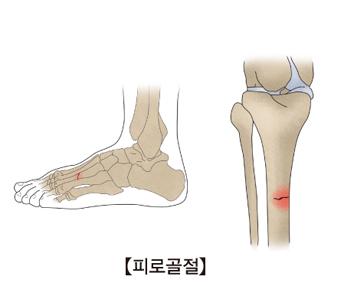

피로 골절(Stress fracture)

관련질환

병리적 골절

,

대퇴 골절

경골과 비골 골절

원위 요골과 척골 골절

골절 후 부정 유합, 불유합

팔죽지 골절

천추골 골절

관련용어

성장판

굳은살